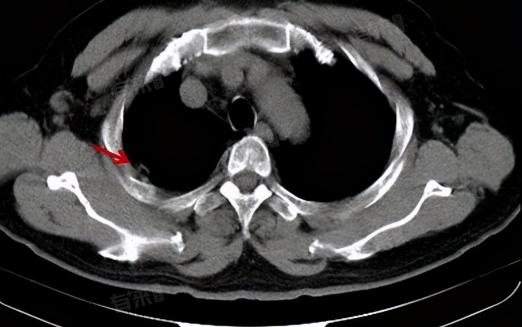

- 胸膜肥厚是胸膜的一种病理改变,主要表现为胸膜增厚、粘连,甚至形成纤维板,通常是由胸膜炎等胸膜疾病在病情稳定后遗留下的。正常情况下,胸膜是很薄的,但在炎症、肿瘤等病理因素的作用下,胸膜会发生增生、肥厚,甚至粘连。胸膜肥厚的程度可以通过胸部X线、CT等影像学检查来评估。